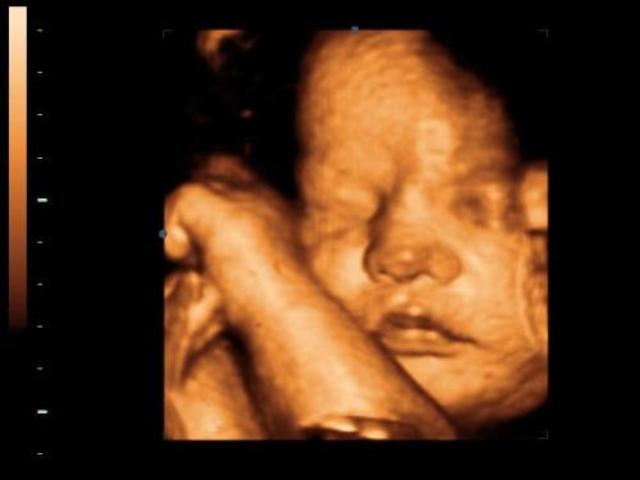

A tizenkettedik hét után már nem embrióról, hanem magzatról beszélünk. A baba ülőmagassága (a fejétől a fenekéig mért érték, CRL) már több mint 4 centiméter, és az arc egyes részei is felismerhetők.